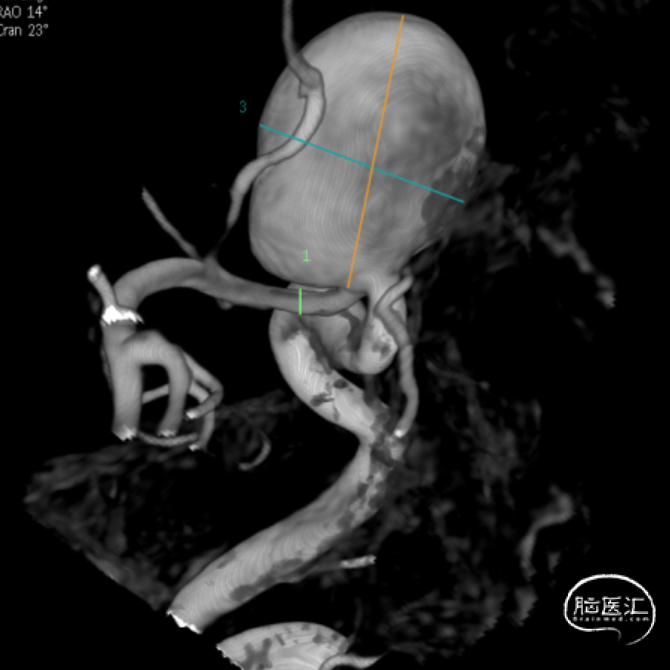

术中DSA造影:右侧颈内动脉3D造影提示:右侧颈内动脉床突旁大型动脉瘤,大小约为20.72×16.33mm,远端血管直径1.92mm,近端血管直径3.48mm。

Headway™ 27 156cm微导管内输送FRED 4017血流导向密网支架,系统远端定位于预计着陆区以远2-3mm处,回撤微导管原位释放支架。释放至动脉瘤颈的迂曲处时,先回撤系统将微导管头端从大弯侧缓慢拉回至血管中央,观察到支架自膨打开后,轻推支架以保证支架贴壁。

①输送导丝头端

②支架远端显影点

③支架微导管头端

④输送导丝尾端显影点

⑤弹簧圈微导管头端

FRED®血流导向密网支架释放至覆盖动脉瘤颈后,通过微导管头端标记点与支架近端标记点预估支架释放的近端着陆点(约为两点之间的40%-60%)。确定近端着陆点处于血管平直区后,平衡释放支架末端,保证支架近端贴壁良好。

①支架远端标记点

②微导管头端标记点

③支架近端标记点

完全释放FRED 4017血流导向密网支架辅助弹簧圈栓塞后,正、侧位及3D造影观察,载瘤动脉通畅、支架贴壁良好、动脉瘤内造影剂滞留。